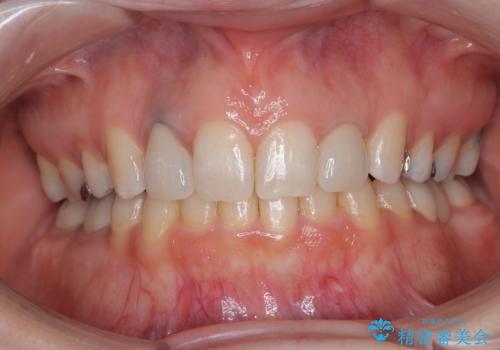

前医で仮歯を装着する前の口元の写真をいただき、咬み合わせや形態を参考にしながら仮歯で仕上がりをイメージし、最終的に満足のいくオールセラミッククラウンを装着することができました。